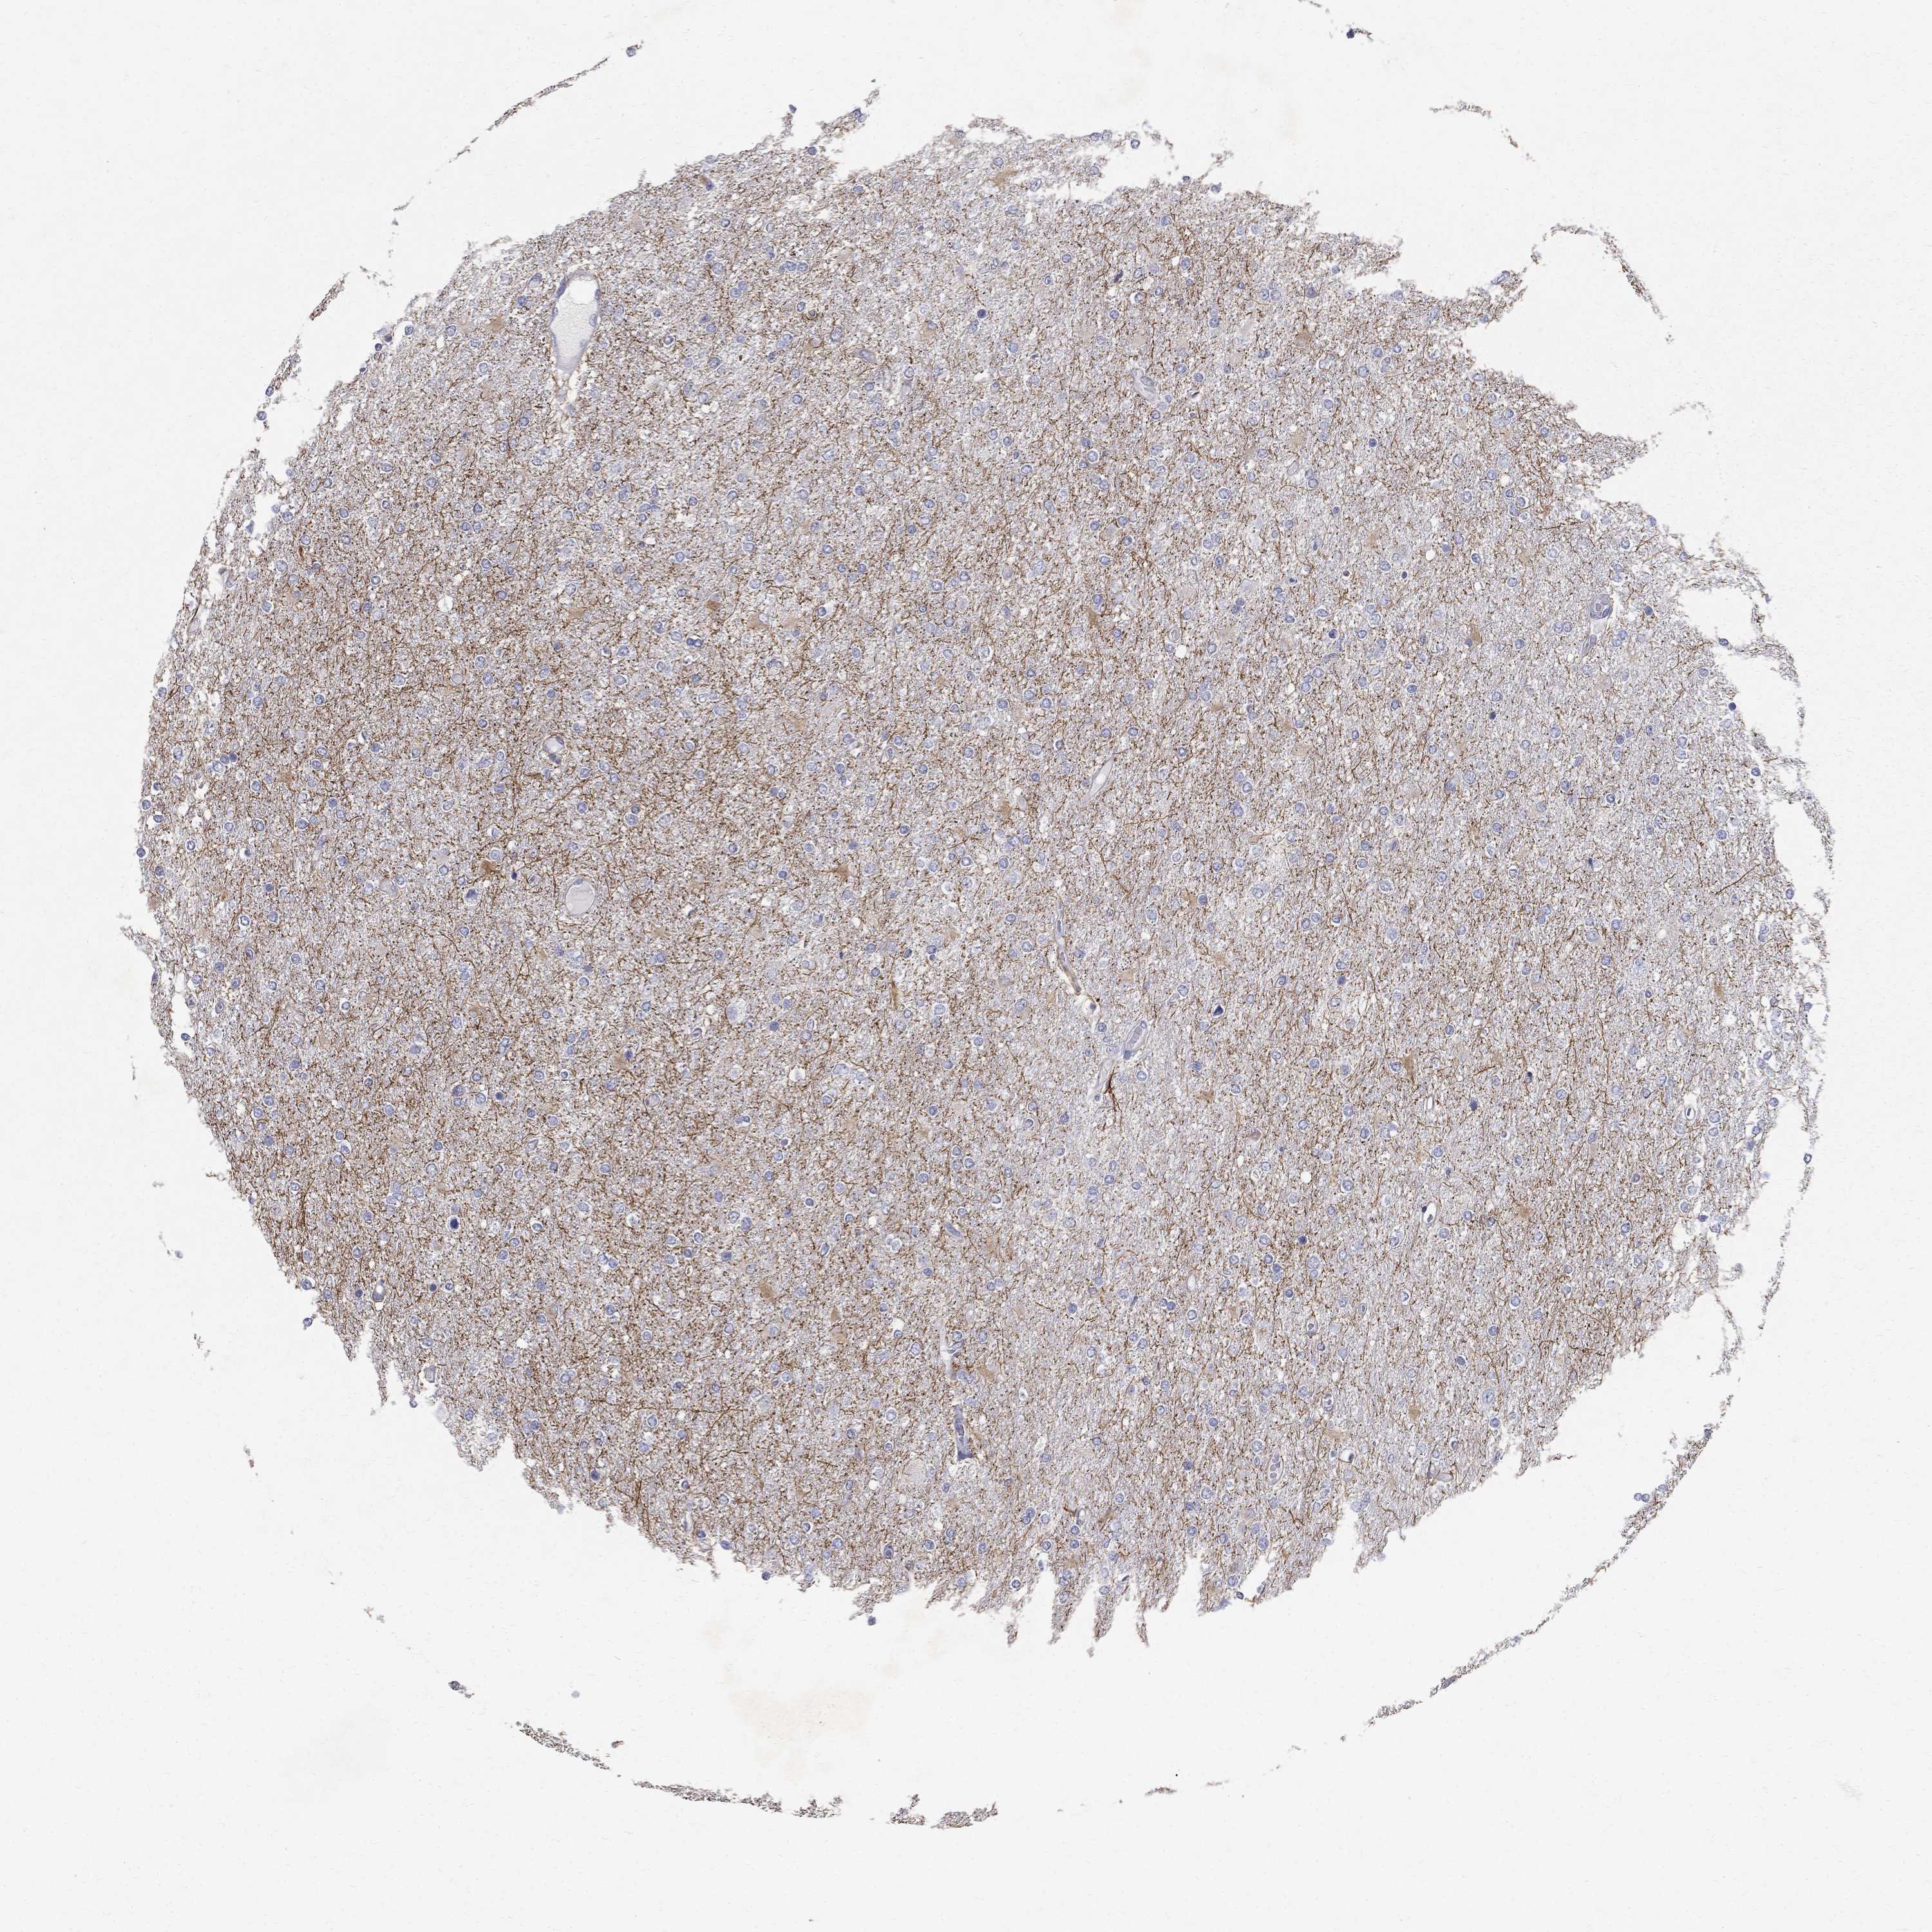

GLIOMA - Protein expressioni

A mouse-over function shows sample information and annotation data. Click on an image to view it in a full screen mode. Samples can be filtered based on level of antibody staining by selecting one or several of the following categories: high, medium, low and not detected. The assay and annotation is described here.

Note that samples used for immunohistochemistry by the Human Protein Atlas do not correspond to samples in the TCGA dataset.

Antibody stainingi

Antibody staining in the annotated cell types in the current human tissue is reported as not detected, low, medium, or high, based on conventional immunohistochemistry profiling in selected tissues. This score is based on the combination of the staining intensity and fraction of stained cells.

Each image is clickable and will lead to virtual microscopy that enables deeper exploration of all samples and also displays staining intensity scores, fraction scores and subcellular localization as well as patient and tissue information for each sample.

Antibody HPA065285

Staining

High

Medium

Low

Not detected

Intensity

Strong

Moderate

Weak

Negative

Quantity

>75%

75%-25%

<25%

None

Location

Nuclear

Cytoplasmic/membranous

Cytoplasmic/membranous,nuclear

Glioma, malignant, Low grade

Glioma, malignant, High grade

Glioma, malignant, NOS